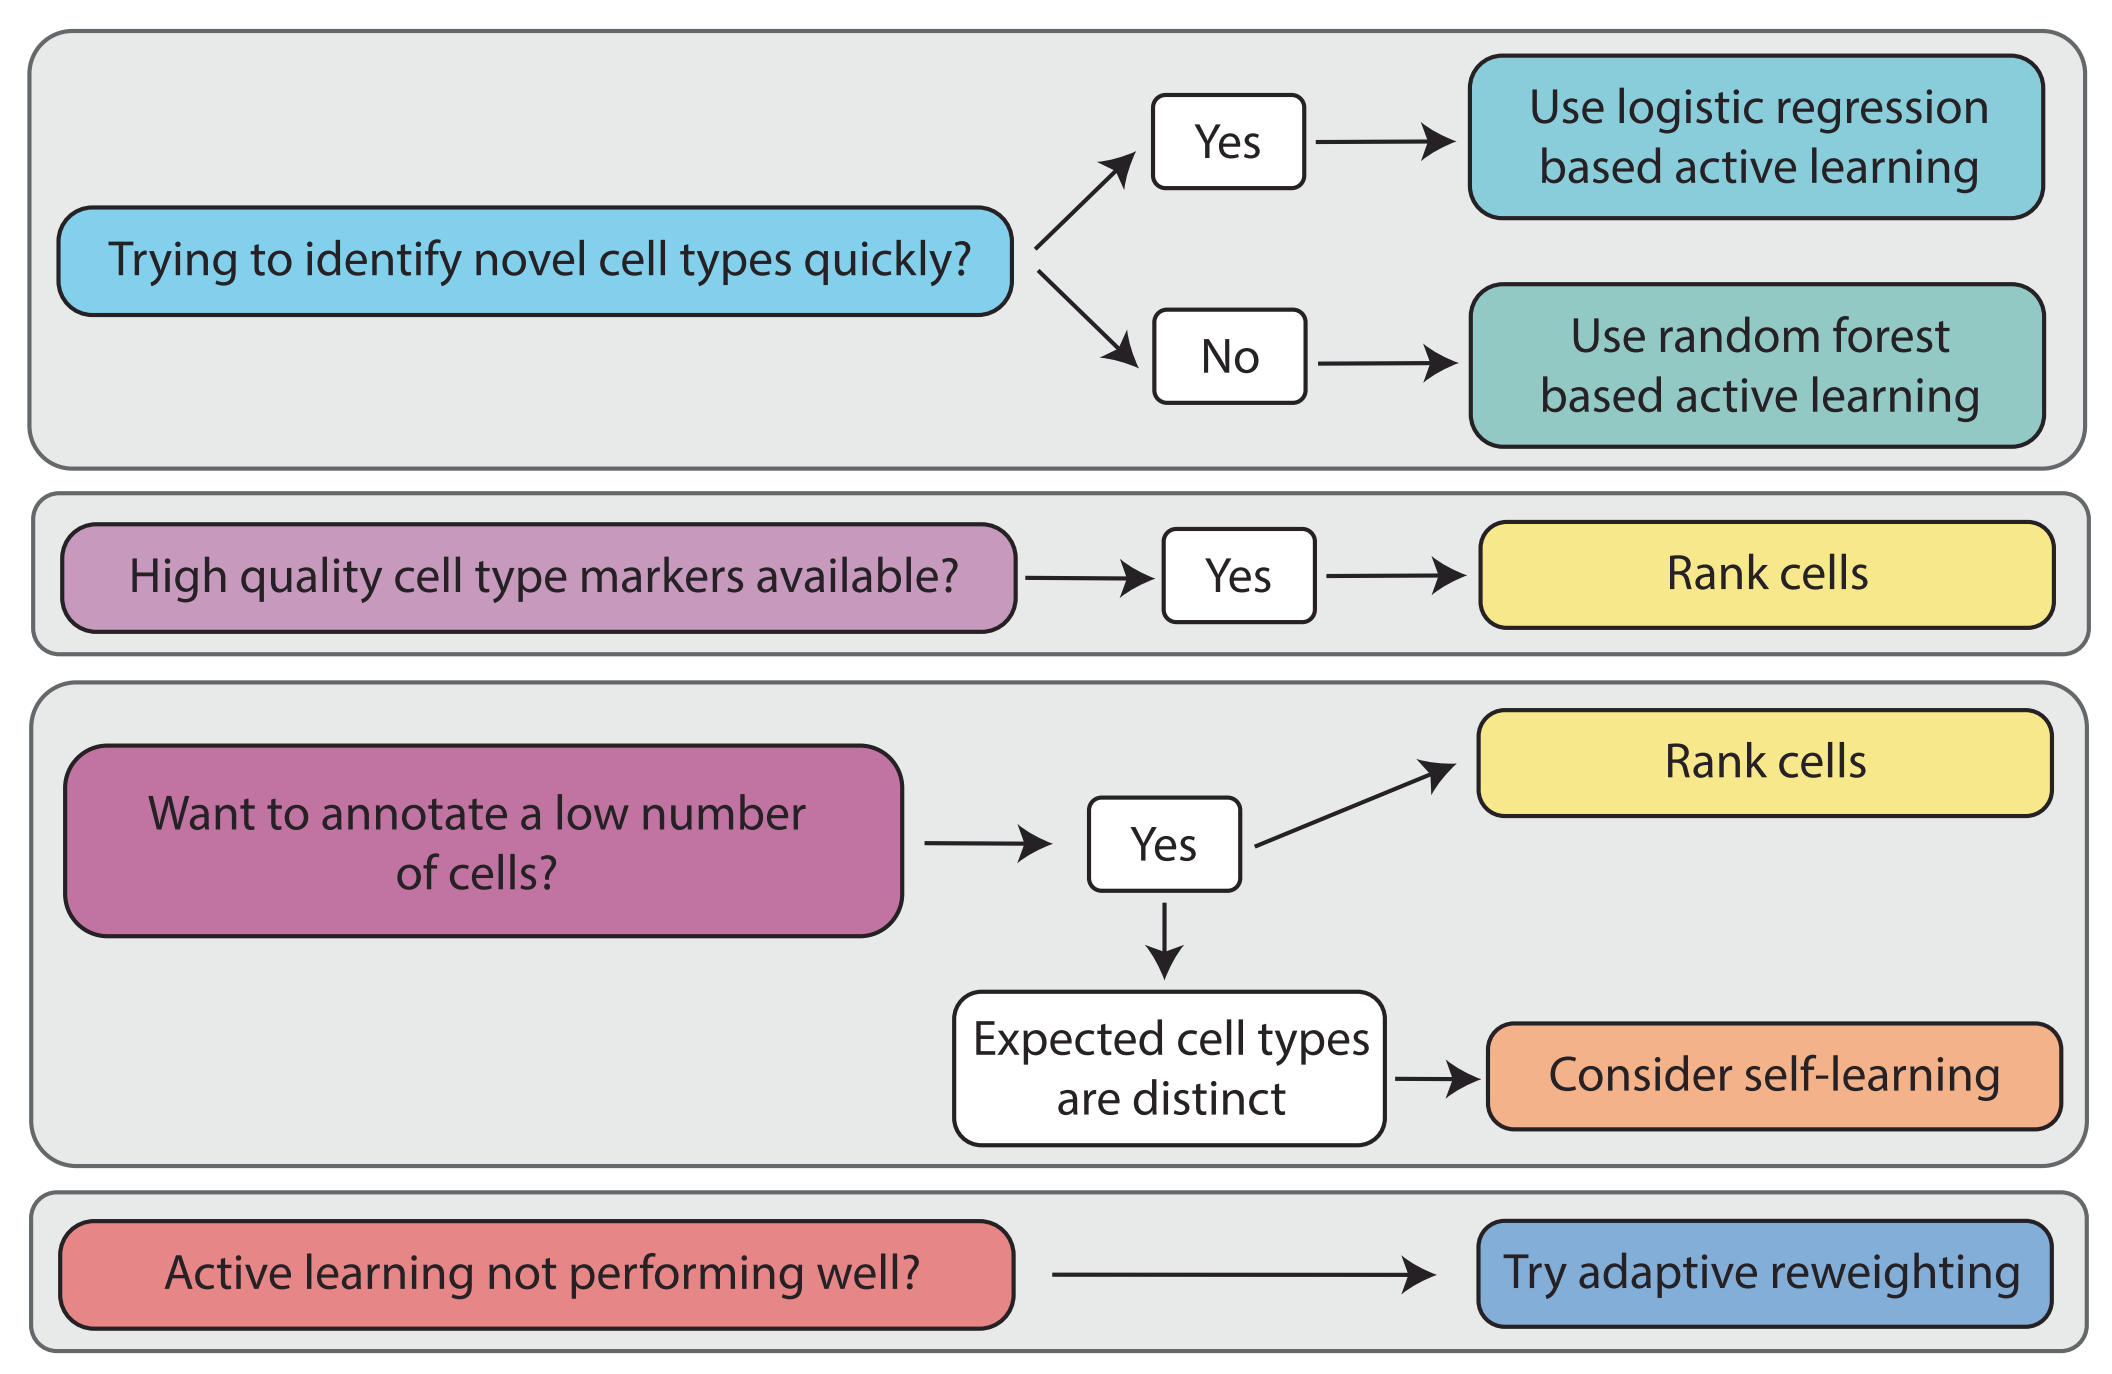

重点关注

一套针对科研实践者的建议,旨在指导他们如何根可用的先验知识、数据集的不平衡性以及希望注释的细胞数量来选择适当的细胞类型选择方法,以辅助基于机器学习的高效注释。

-

数据集不平衡的处理:当某些细胞类型在数据集中占比较少时,可能需要特别设计的算法来确保这些稀有类型的准确注释。

-

注释数量的考量:如果用户只需要注释少量细胞,可能会推荐使用主动学习策略;而对于大规模注释任务,则可能推荐使用自监督学习或其他更自动化的方法。

-

效率与准确性的平衡:讨论在选择方法时如何平衡注释效率和结果准确性,因为不同的方法可能在这两方面有不同的表现。

-

实验设计的考虑:如果实验需要高度精确的细胞类型注释,可能需要采用更为保守和细致的注释策略。

-

资源和时间的限制:考虑用户在资源(如计算能力、资金)和时间上的限制,推荐在这些限制条件下最可行的方法。